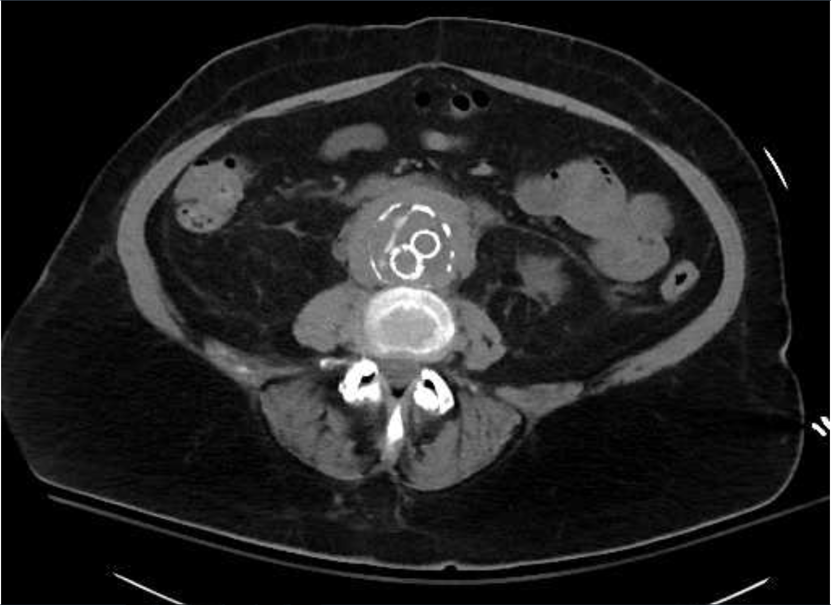

Case 2: A 70 year old male presented in November 2017 after being found to have acute abnormalities in his lab work found by Nephrology as an outpatient. He follows with Nephrology and Urology since having been diagnosed with retroperitoneal fibrosis and had bilateral ureteral stents placed. The patient’s Creatinine level was found to be 8.26mg/dL, with baseline around 3.0mg/dL. In the Emergency Room he was acidotic with a bicarbonate level of 13mmol/L, other lab results included a BUN level of 144mg/dL, Potassium level at 5.3mmol/L, Magnesium level of 1.0mg/dL. A bicarbonate drip was started. Nephrology and Urology were called and tried placing ureteral stents, but failed due to fibrotic tissue surrounding the ureters. Bilateral nephrostomy tubes were placed, and patient’s renal function initially started to improve, but started to decline again. He started showing signs of uremic encephalopathy, so a permacath was placed and he started hemodialysis. His renal function improved significantly. This patient was diagnosed with retroperitoneal fibrosis about three months status-post his EVAR.